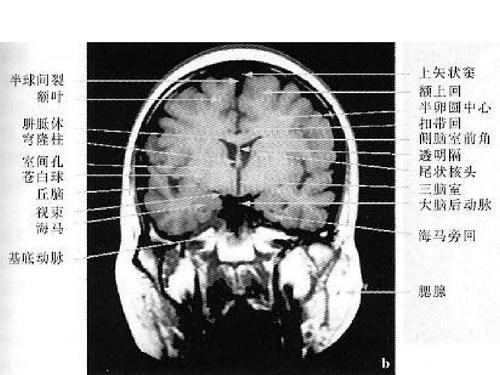

脑部主要结构mri横断位解剖

高清mri图颅脑磁共振mri解剖